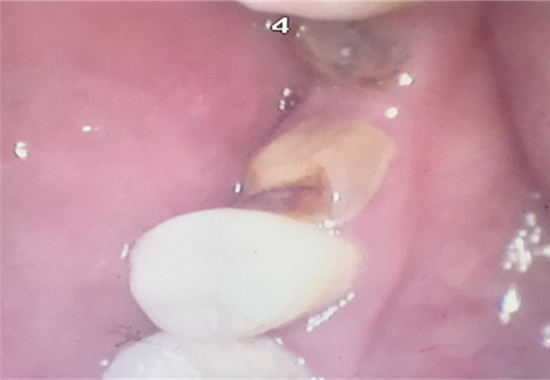

赵先生内窥镜检查:牙齿仅剩残根

当天,像张伯伯和赵先生这样的居民还有很多,因为口腔知识的缺乏,很多人陷在“洗牙会让牙齿松动”、“牙痛不是病,痛起来真要命”等认识误区里面,许多人对口腔疾病视而不见,任其发展。面对市民们各式各样的口腔健康问题,福州口腔医院科尔口腔医生耐心的回答咨询者的每个问题,如果遇到不容易讲清楚的问题,还亲自示范。